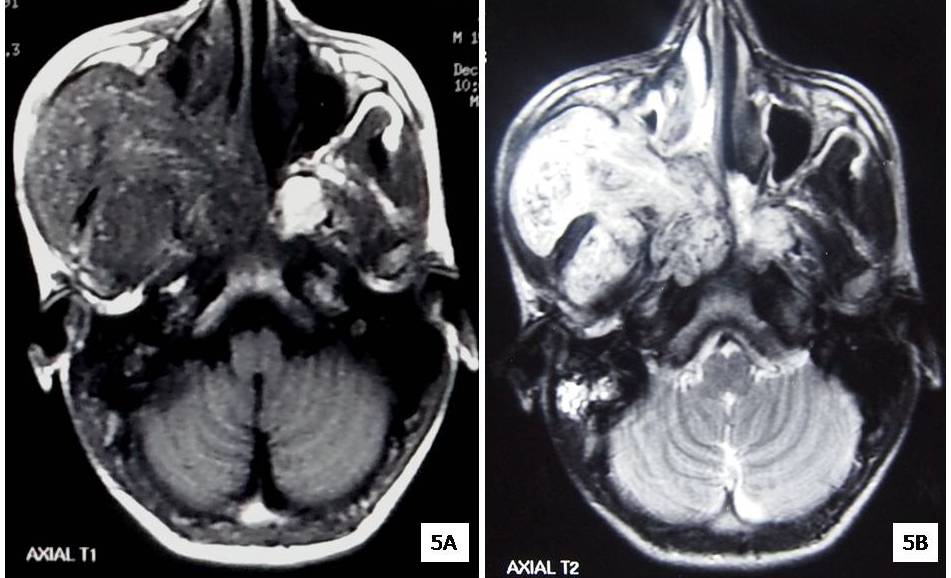

Magnetic Resonance Imaging showed large mass lesion measuring 8cm x 8cm x 10.5cm, seen in right pterygopalatine fossa causing widening of fossa. Bowing & compression of right maxillary sinus with extension of the lesion into nasopharynx & right posterior nasal cavity through nasopalatine foramen was also seen [Table/Fig-5a]. Extension into orbit & right cavernous sinus with multiple flow voids are representative of a vascular lesion [Table/Fig-5b]. Angiogram showed multiple small & medium vessels supplied by right facial & lingual artery measuring 80cm x 54cm x 72 cm [Table/Fig-6a&b].

a) Axial section of T1 weighted Magnetic Resonance imaging reveals a large, ill defined heterogeneous enhancing mass lesion involving right pterygopalatine fossa. b) Axial section of T2 weighted Magnetic Resonance imaging reveals large ill defined hyper intense mass lesion involving right pterygo-palatine fossa. Multiple flow voids are also noted